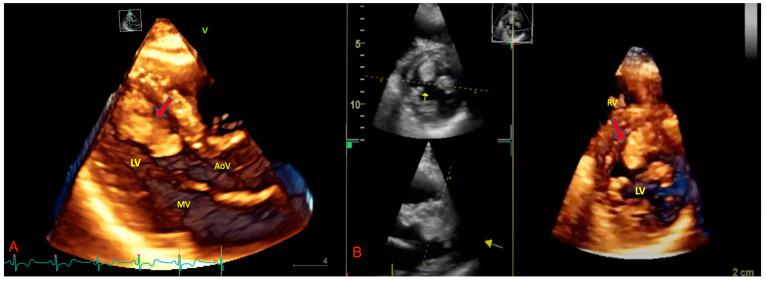

Primary malignant cardiac tumors are rare, with a prevalence of about 0.01% among all cancer histotypes. At least 60% of them are primary soft tissue sarcomas of the heart (pSTS-h) that represent almost 1% of all STSs. The cardiac site of origin is the best way to classify pSTS-h as it is directly linked to the surgical approach for cancer removal. Indeed, histological differentiation should integrate the classification to provide insights into prognosis and survival expectancy of the patients. The prognosis of pSTS-h is severe and mostly influenced by the primary localization of the tumor, the difficulty in achieving complete surgical and pharmacological eradication, and the aggressive biological features of malignant cells. This review aims to provide a detailed literature overview of the most relevant issues on primary soft tissue sarcoma of the heart and highlight potential diagnostic and therapeutic future perspectives.